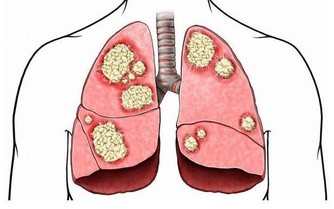

4. 黑棗

營養分析:

泡製而成的黑棗是大棗乾品

其補益作用大於鮮品,

相比紅棗,它的養血補中作用更強。

黑棗含有豐富的維生素

有極強的增強體內免疫力的作用,

並對賁門癌、肺癌、吐血有明顯的療效。